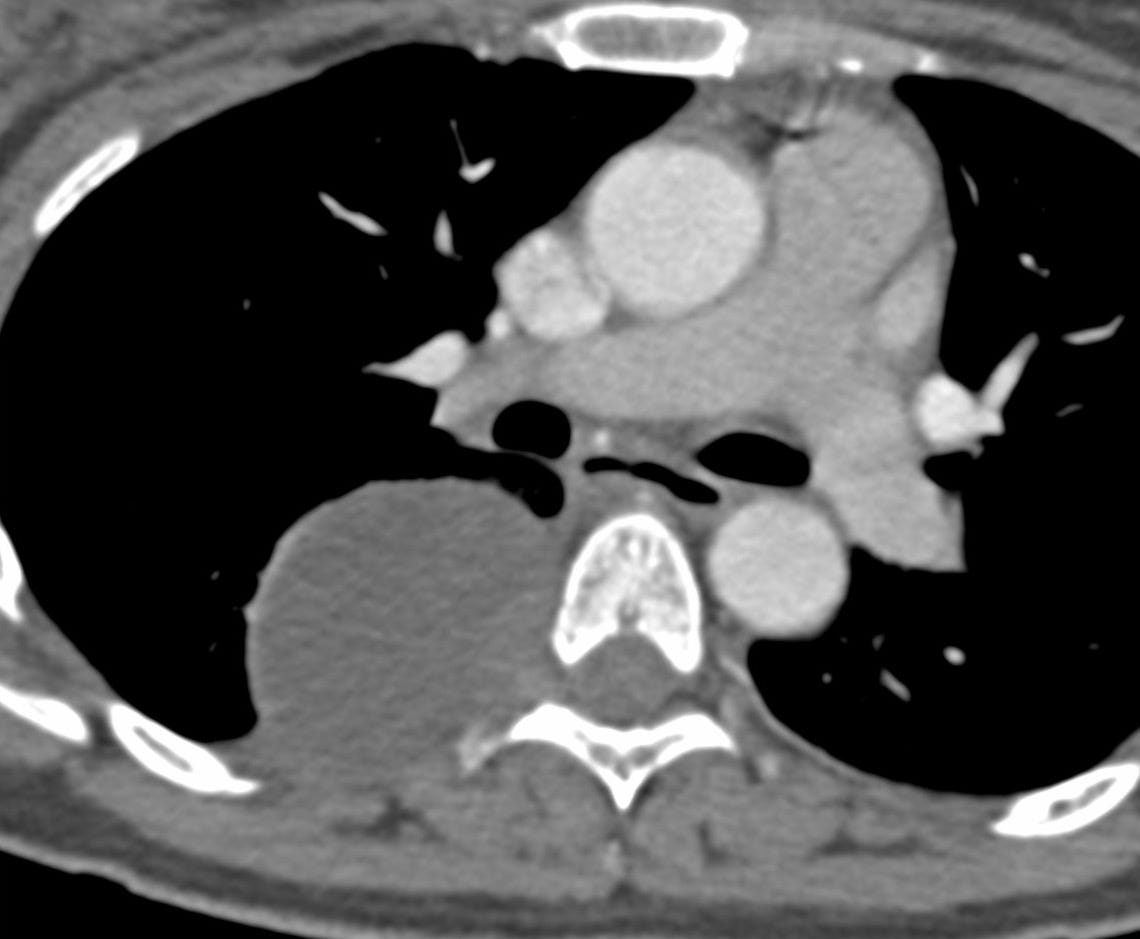

A 39-years old was found to have a mass in the chest on a CT chest done for COVID-19.

What is the likely diagnosis?